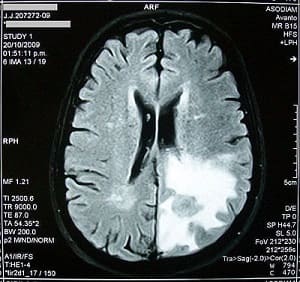

Tumores cerebrales

Un tumor cerebral se produce por el crecimiento incontrolado de una masa de células que crecen anormalmente dentro del cerebro.

Tumor cerebral visto a través de una imagen electrónica